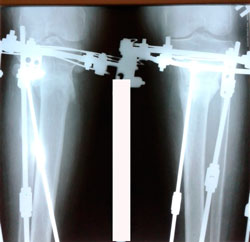

Исходник - 35 лет.

Дата операции - 06.01.2020 г.

перед крутками

3 - ий день круток

В процессе работы

на фиксации